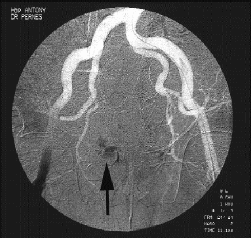

Mise au point Traumatismes ostéovasculaires : Stratégie thérapeutique , J. Marzelle Hôpital Privé d'Antony, 1 rue Velpeau, 92160 Antony, France , P. Trévidic Paris , JM. Pernes Hôpital Privé d'Antony, , S. Kovarsky Hôpital Privé d'Antony, , H. Borie Hôpital Privé d'Antony, N°104 - Mai 2001 ● 19 min de lecture